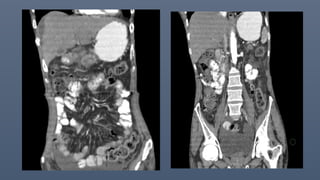

PERITONEAL NEOPLASMS

• Varying degrees of peritoneal thickening and soft tissue infiltration,

Mass forming lesions, ascites, calcifications.

Peritoneal metastatic disease is the most common cause of peritoneal

neoplasm

Peritoneal carcinomatosis

• Primary - gastric ,colonic ,appendiceal ,pancreatic ,biliary tract ,and

ovary

• Ascites – early and common feature

• Sheet like growth or infiltration along the mesentry or omentum.

• Thickening and/or enhancement of the peritoneal layers

• Peritoneal implants as suface nodularity /discrete masses